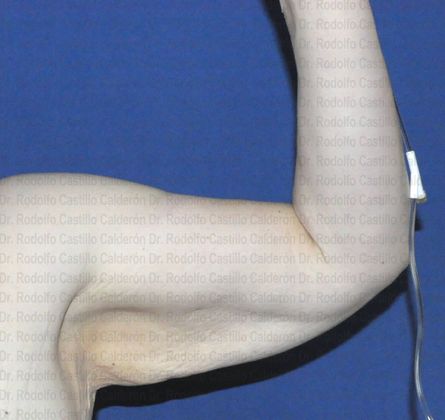

MyBestBodyEver!

Dr. Castillo is a board-certified plastic surgeon with over ten years of experience performing cosmetic surgery. Our state-of-the-art facility is designed with the latest medical technology to ensure patient comfort and safety. Dr. Castillo is affiliated with: